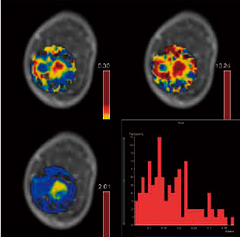

●簡便な薬物動態解析機能

乳腺ダイナミック画像を用いた質的・広がり診断に加え,近年の治療技術の進歩により,治療効果判定が重要視されています。シーメンスは,従来のダイナミック画像を用いたwash-in/out診断に加え,濃染域をより詳細に評価できる薬物動態解析ソフトである“syngo Tissue 4D”を提供します。自動算出されるKtrans,kep,ve,iAUC,Histogramを用いることで,組織内情報を詳しく診断することが可能です(図2)。

図2 syngo Tissue 4D